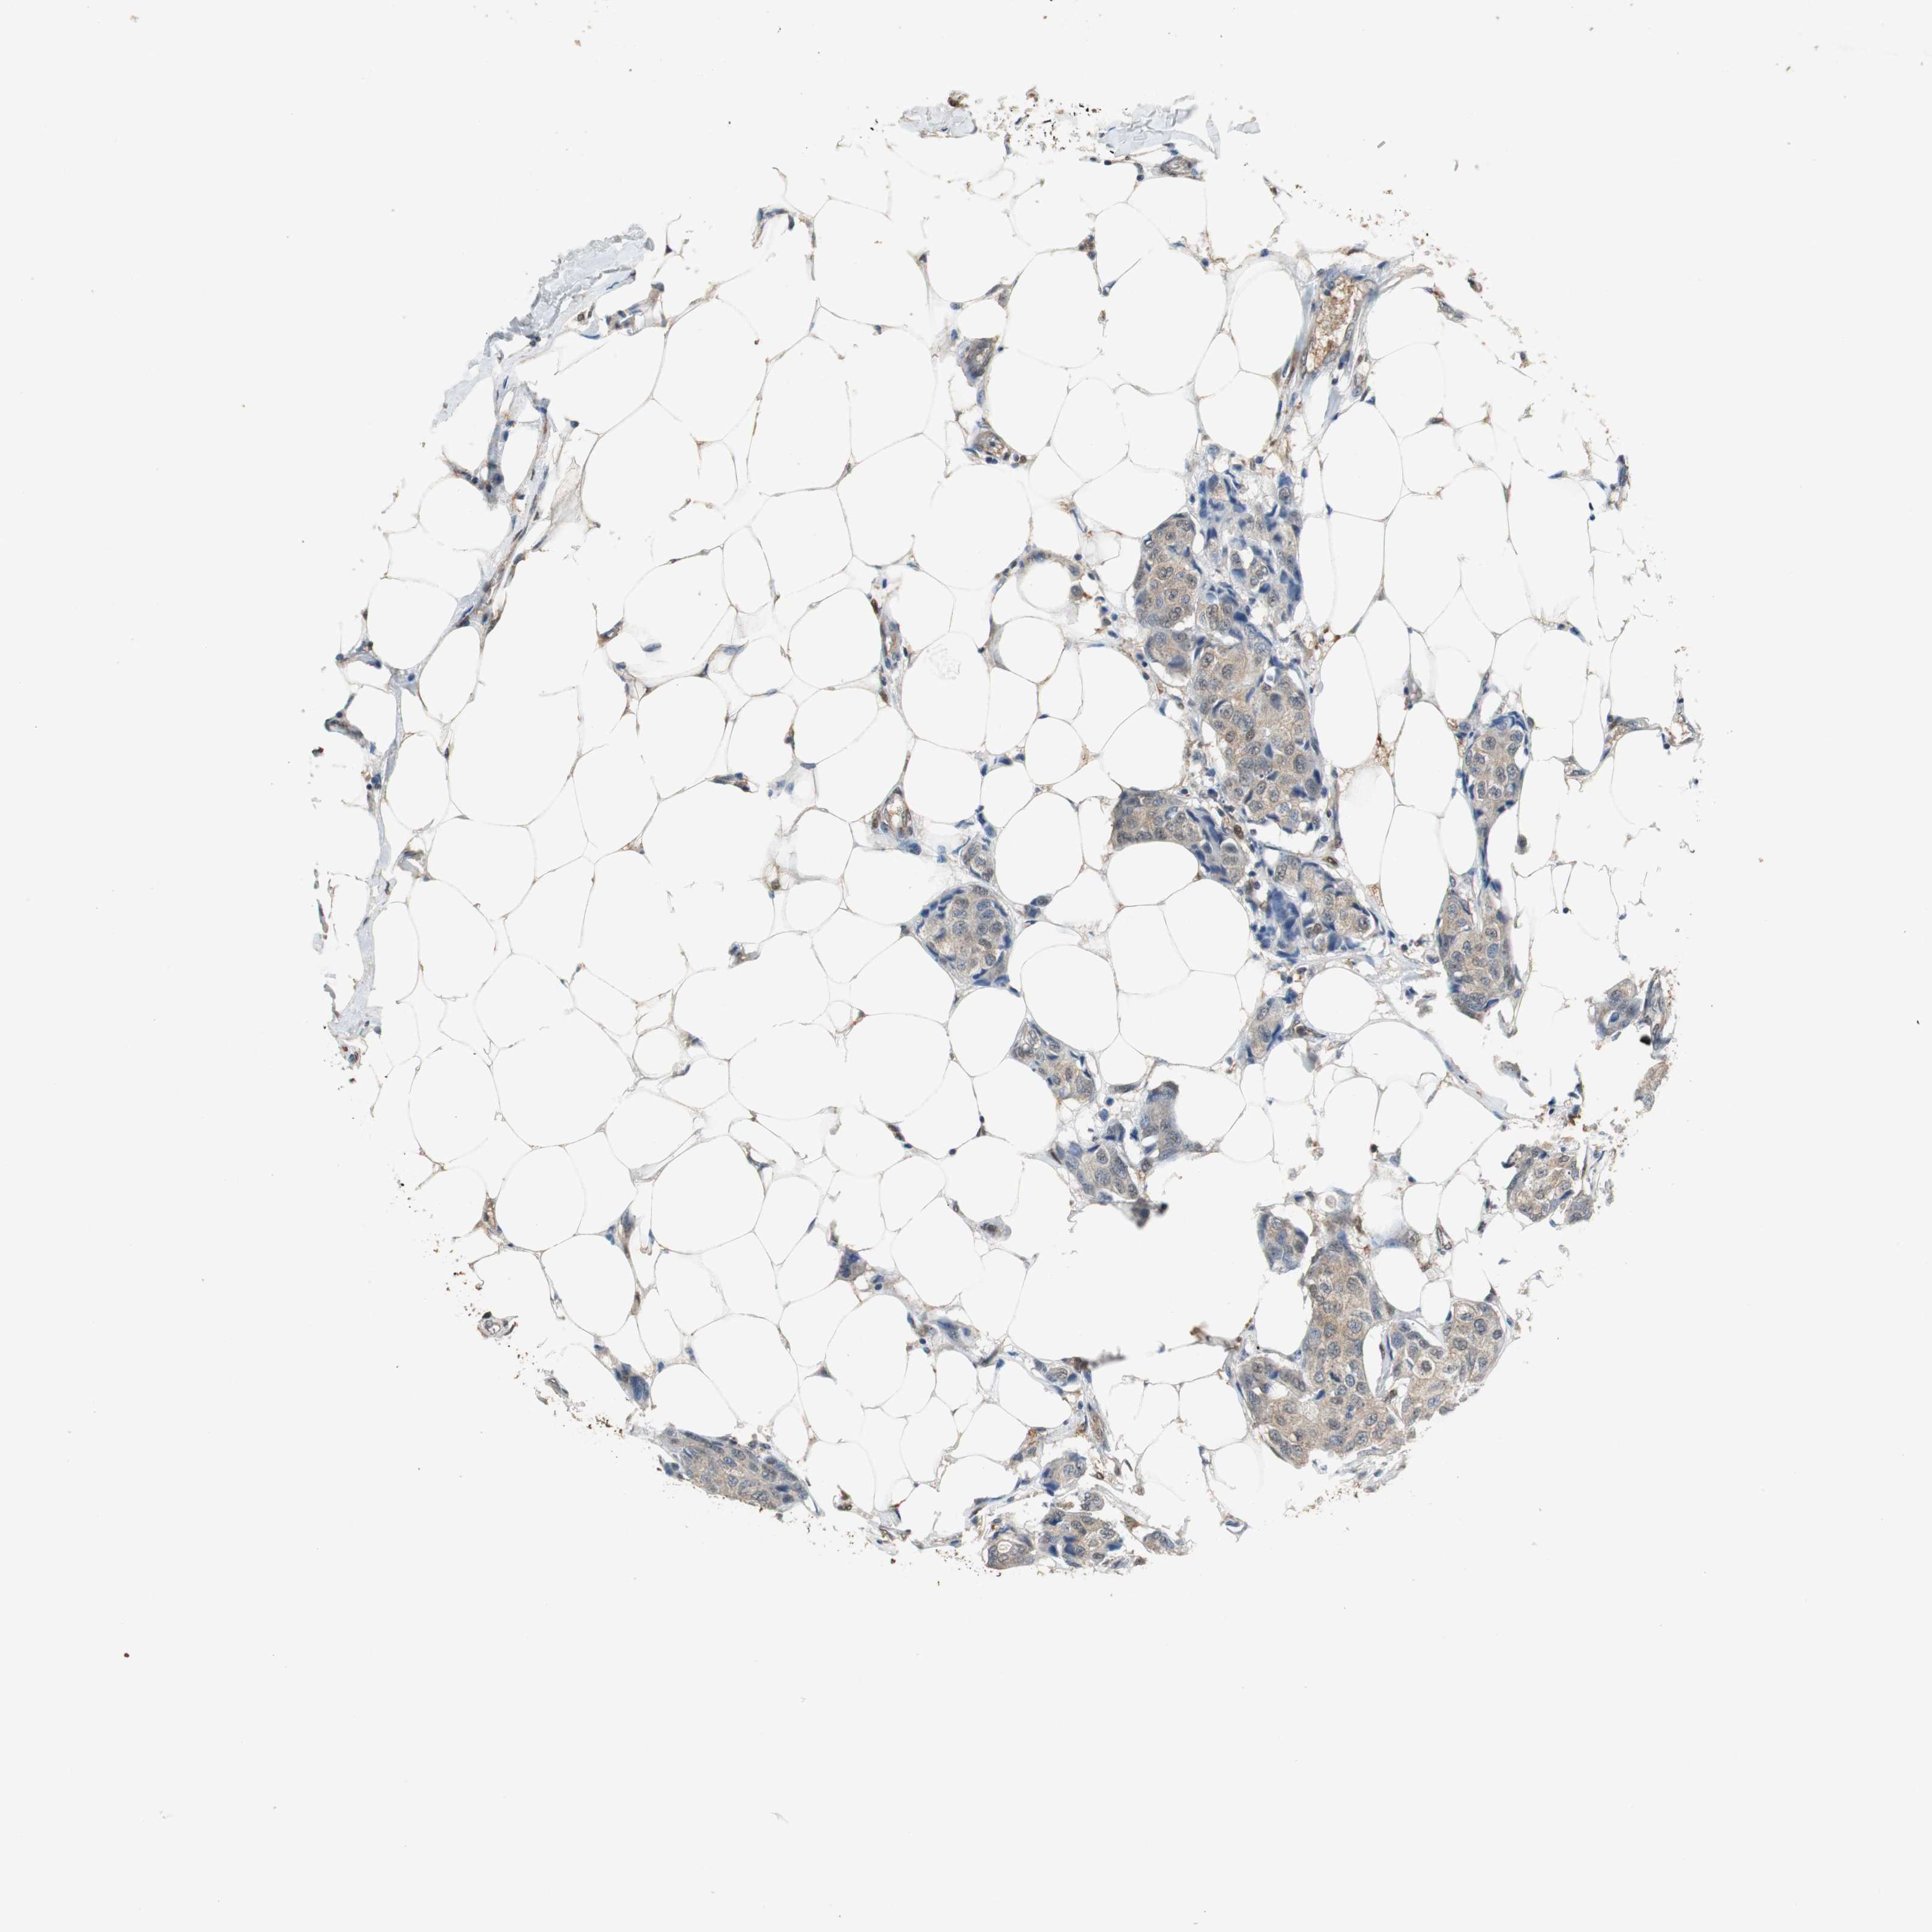

BRCA TCGA BRCA VALIDATION PROTEIN EXPRESSION